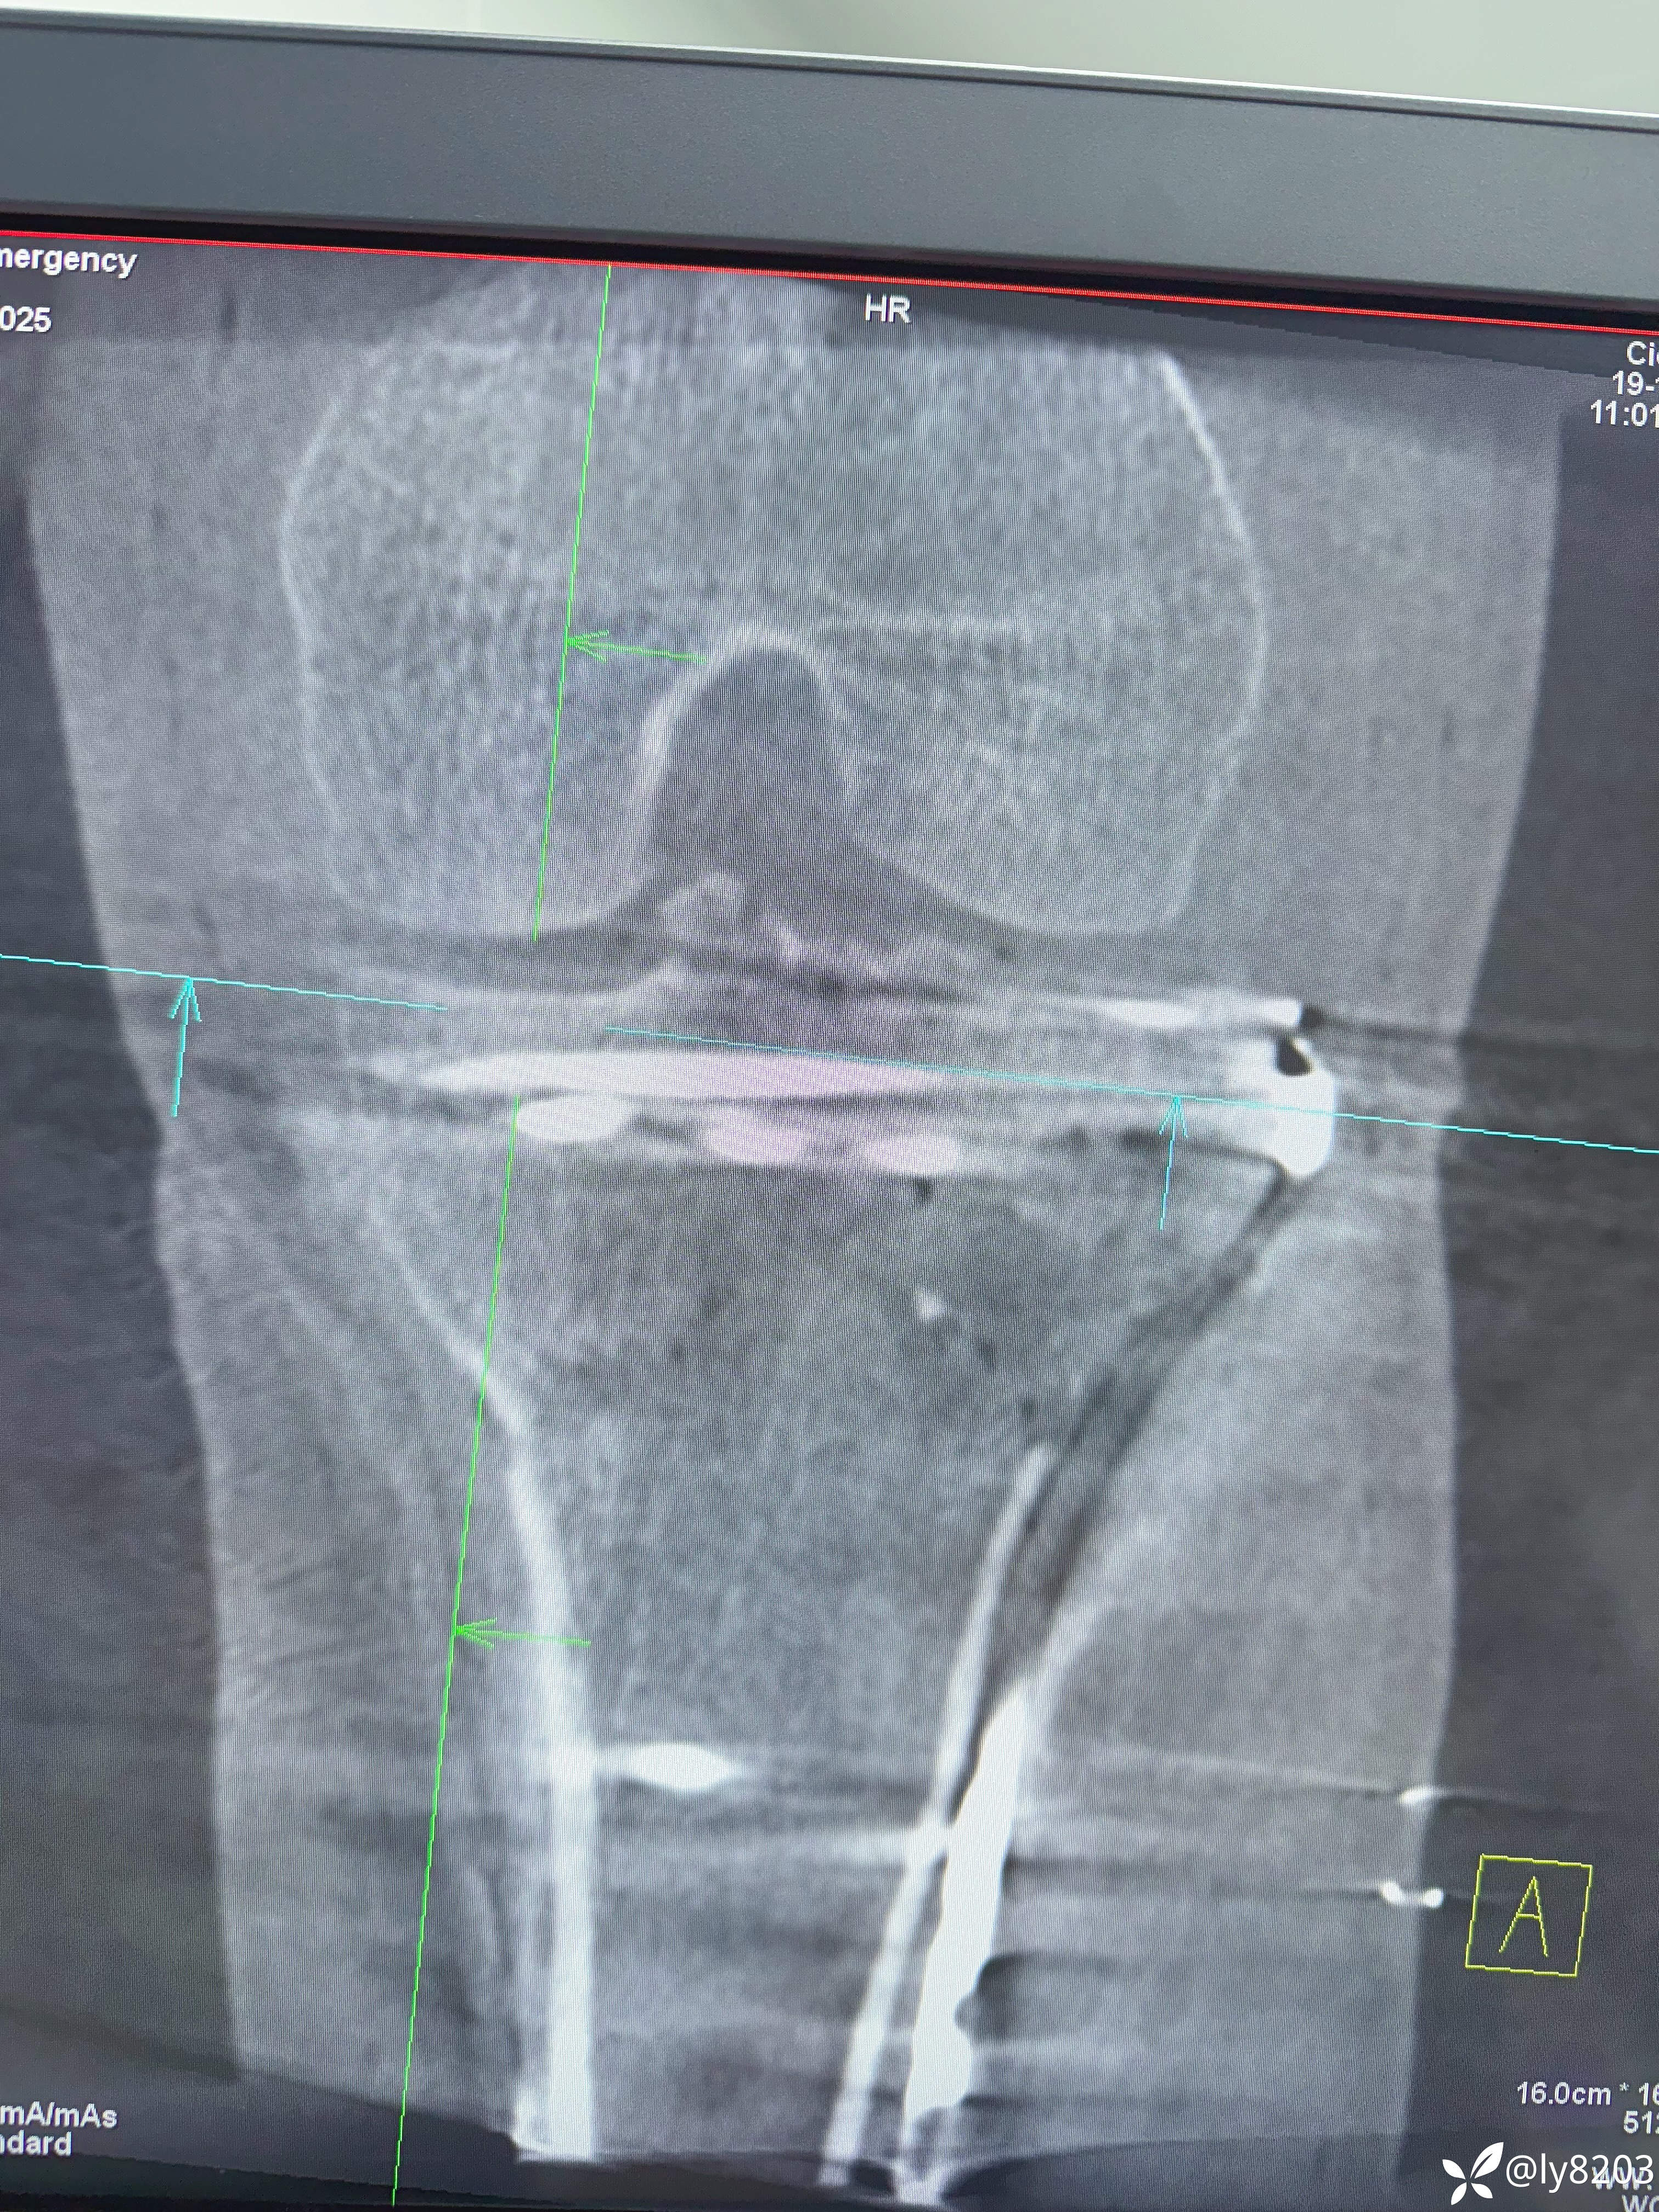

术后影像

术后平片

这个难点在后外侧游离骨块。按胡老师的方法,先将外侧平台用两个弯钳抬起,与前髁间棘对齐后克氏针固定,再从外侧副韧带后缘用骨拨托住并往前顶,从关节线用弯钳从前面抬,没成功,随即改变方案,用胡式顶棒外侧经皮顶,后侧骨块解剖复位,后缘与外侧平台丝滑对齐,克氏针固定。剩下就是常规操作了。以往都是大切口,截骨处理后外侧,胡教授的方法避免了切口大,创伤大。有利于加速康复。